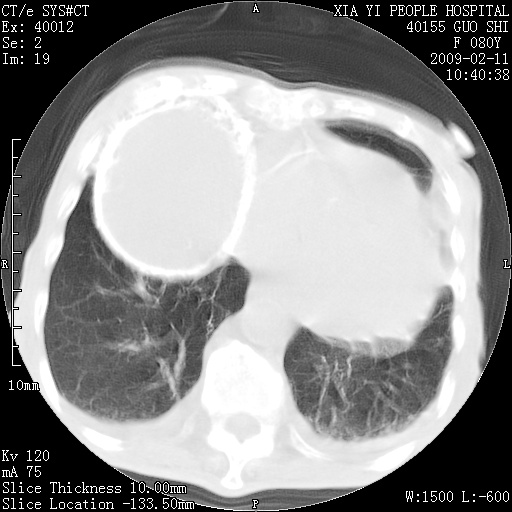

以下是引用随光逐影在2009-2-16 16:34:00的发言:[br]1)考虑右前纵隔皮样囊肿。2)双侧少量胸腔积液。

以下是引用zjzjr在2009-2-16 17:30:00的发言:[br]支持囊性畸胎瘤 双侧少量胸腔积液。